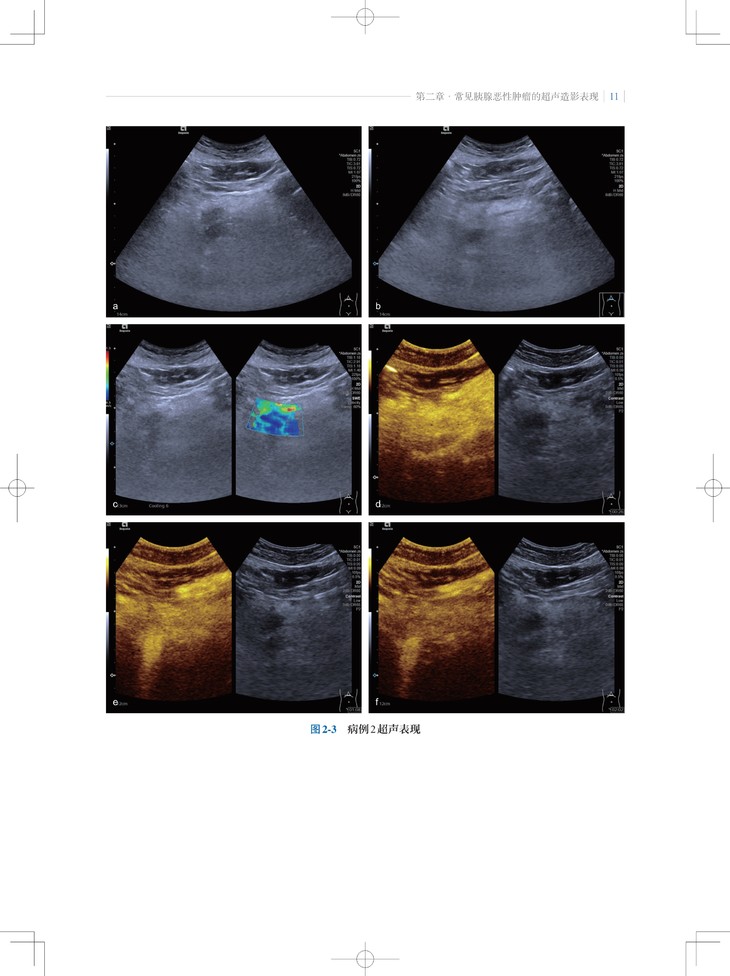

本书是“东方超声文库”系列之一,介绍了超声造影剂和实时超声造影技术在胰腺肿瘤诊疗领域的最新应用。内容包括胰腺肿瘤的超声造影表现特点、诊断要点,超声造影在随访胰腺癌非手术治疗、预测胰腺切除术后并发胰瘘、胰腺癌微创介入治疗中的应用;此外,通过与胰腺肿瘤的CT、MRI等影像学表现的对比,让读者对超声造影检查技术有更全面的认识。

2. 内容实用:超声造影不但提高了胰腺肿瘤定性诊断的准确性,而且能反映胰腺肿瘤微血管的血流动力学改变,本书对从事胰腺肿瘤诊断和治疗的各领域、各级临床医师有实用指导意义。

3. 编写方式契合临床:不仅有胰腺肿瘤造影影像图,还有与CT/MRI等影像学表现的对比及手术照片。